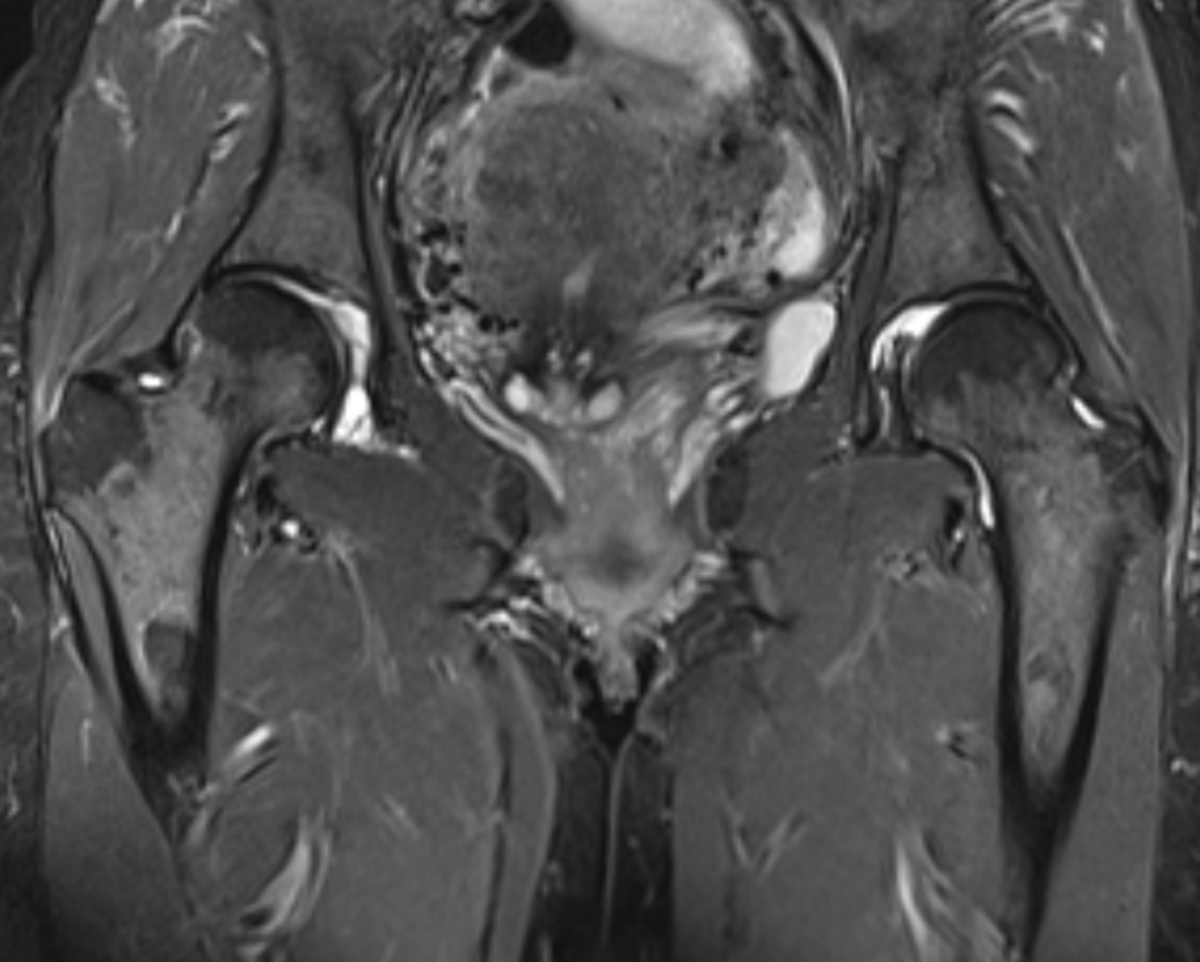

#CaseOfTheWeek‼️🥳‼️ ☢️🩻☠️Case#22☠️🩻☢️ #Mass 📲➡️➡️#Diagnosis❔❓❔ #FOAMRad #RadEd #MedEd #OrthoEd #OrthoTwitter @ssr_rwg @UWRadRes @ISSVA_org